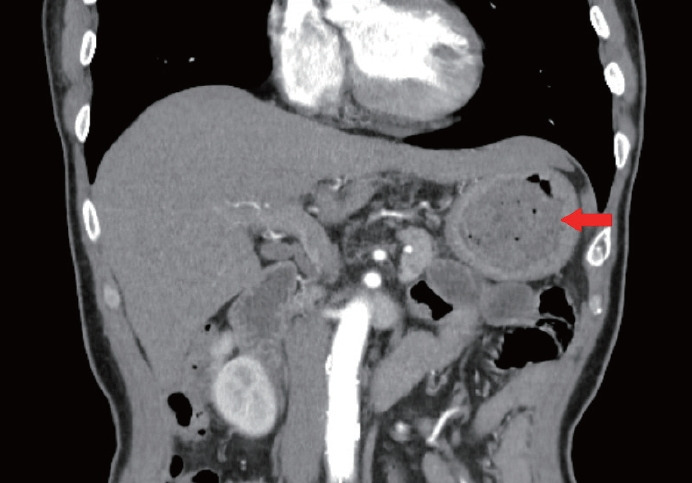

牛黄是一种难以消化的物质,可引起胃肠道并发症,如阻塞和穿孔。我们报告的情况下,60岁的男子与2型糖尿病和十二指肠溃疡手术史。患者出现大量胃植粪,引起持续性消化不良和胃脘痛。胃镜检查证实胃角处有10厘米的植物性牛黄和1.5厘米的活动性溃疡。为了软化牛黄,病人服用了可口可乐和纤维素酶。这种治疗方法显著降低了牛黄的硬度,使其能够成功地使用常规设备进行内窥镜碎裂。在三次内窥镜检查中,牛黄被粉碎成小于1厘米的碎片并被取出;此后,胃溃疡完全愈合。本病例说明了将可口可乐和纤维素酶的作用与内窥镜方法结合治疗大牛黄的有效性,为社区卫生保健机构提供了一种手术方法的替代方法。

Bezoars are indigestible masses that can cause gastrointestinal complications such as obstructions and perforations. We report the case of a 60-year-old man with a history of type 2 diabetes mellitus and duodenal ulcer surgery. The patient developed a large gastric phytobezoar that caused persistent dyspepsia and epigastric pain. Upper endoscopy confirmed a 10-cm phytobezoar and a 1.5-cm active ulcer at the gastric angle. To soften the bezoar, Coca-Cola and cellulase were administered to the patient. This treatment significantly reduced the bezoar's hardness, permitting its successful endoscopic fragmentation using conventional devices. Over three endoscopic sessions, the bezoar was fragmented into pieces smaller than 1 cm and removed; thereafter, the gastric ulcer healed completely. This case illustrates the effectiveness of combining the actions of Coca-Cola and cellulase with endoscopic methods to treat large bezoars, providing an alternative to surgical approaches in community healthcare settings.